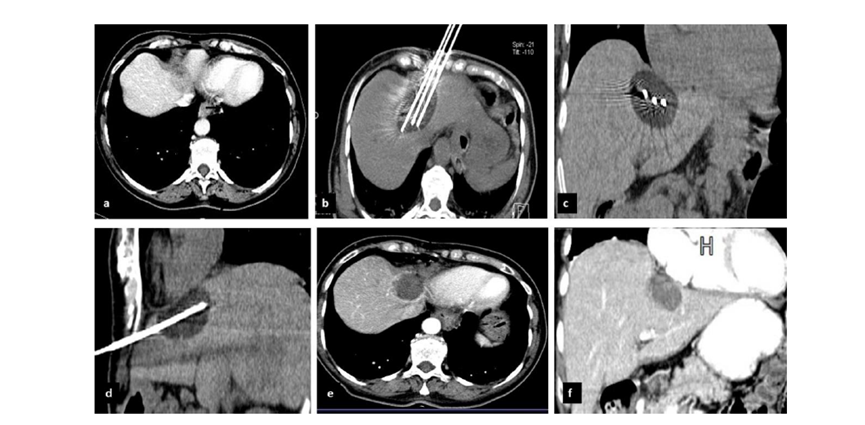

CT引導(dǎo)的冷凍消融

(b) 冷凍消融術(shù)中影像顯示冰球完全覆蓋病變。(c) 19個月后隨訪,沒有發(fā)生局部腫瘤進展。完全消融率為97%(66/68);2名患者均接受了額外的冷凍消融,隨后實現(xiàn)完全消融。平均隨訪期為 12.8 個月(范圍:3-27 個月)。所有患者均接受影像復(fù)查(CT 或 MRI)。11個病灶(16.2%)檢測到局部腫瘤進展,6、12和18個月時的累積局部腫瘤進展率分別為4%、8.2%和20.5%。8例出現(xiàn)遠處肝內(nèi)或肝外病變的患者接受經(jīng)動脈化療栓塞、經(jīng)動脈化療栓塞加射頻消融治療或全身化療。

( a ) 軸向 MRI 和 ( b ) 軸向 CT 顯示肝S8段有一個16mm的病灶,鄰近肝緣。( c )冷凍消融期間CT顯示放置了2個冷凍探針,低密度冰球包圍病灶。(d)術(shù)后1個月隨訪 CT顯示冰球?qū)?yīng)的壞死區(qū)域,未見復(fù)發(fā)。(e)術(shù)后6個月的CT,壞死區(qū)域縮小,未見復(fù)發(fā)。(f)與基線影像(g)相比,12個月后的FDG-PET/CT顯示未見FDG攝取。

62歲女性,肝轉(zhuǎn)移(卵巢癌)腫瘤的完全消融病例(a)軸向CT顯示病變位置毗鄰心臟和上腔靜脈(黑色箭頭)。(b)術(shù)中軸向CT掃描:使用三個冷凍探針。1個月后的軸向(e)和冠狀位(f)增強CT掃描顯示低密度區(qū)域,由于肉芽組織反應(yīng)引起的邊緣增強。